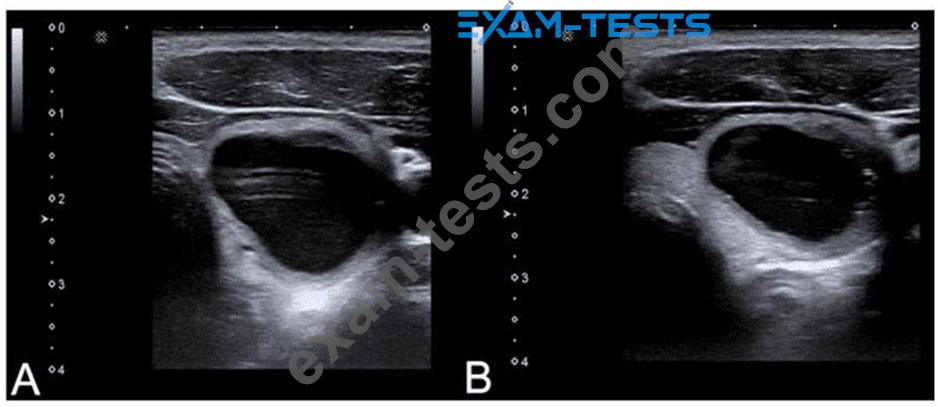

Which adjustment will reduce the artifact in the cystic lesion in image A resulting in image B?